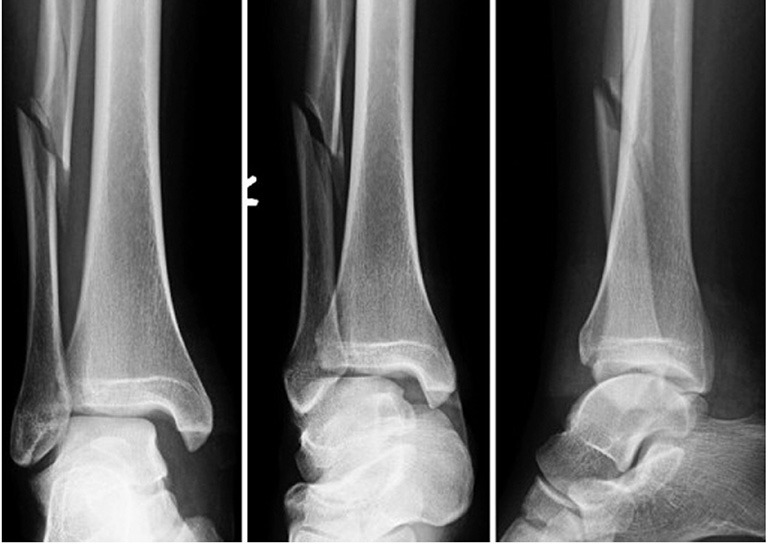

Gãy 1/3 dưới xương mác là một chấn thương thường gặp trong các tai nạn thể thao hoặc tai nạn giao thông. Mặc dù xương mác không phải là xương chính trong việc chịu lực của chân, nhưng nếu không được điều trị đúng cách, có thể dẫn đến các biến chứng không mong muốn. Vậy gãy 1/3 dưới xương mác có nguy hiểm không?

Gãy 1/3 dưới xương mác mặc dù không phải là một chấn thương quá nghiêm trọng như gãy xương đùi hay xương chày, nhưng nếu không được điều trị đúng cách, có thể dẫn đến các biến chứng nguy hiểm.

Gãy 1/3 dưới xương mác, nếu không kèm theo các biến chứng như gãy lệch hoặc ảnh hưởng đến các cấu trúc xung quanh, thường không gây nguy hiểm nghiêm trọng và có thể tự lành mà không cần phẫu thuật. Thời gian hồi phục của xương là khoảng 6 - 8 tuần, và mặc dù xương sẽ liền, quá trình phục hồi hoàn toàn trên phim X-quang có thể kéo dài đến 6 tháng. Tuy nhiên, trong suốt thời gian này, việc bảo vệ xương bằng nẹp và tránh va chạm, chấn thương là rất quan trọng.

Khi gặp phải chấn thương gãy 1/3 dưới xương mác, nhiều người thường băn khoăn liệu có cần bó bột hay không. Thực tế, trong trường hợp gãy xương mác mà không ảnh hưởng đến các cấu trúc quan trọng như gọng chày sên (phần tiếp xúc giữa xương mác và các xương khác), việc bó bột không phải là phương pháp điều trị bắt buộc. Thay vào đó, bác sĩ sẽ khuyên bệnh nhân sử dụng các biện pháp bảo vệ nhẹ nhàng hơn, như nẹp hoặc nẹp cố định để tránh các va chạm, tác động mạnh lên khu vực xương đang lành. Điều này giúp tránh nguy cơ gãy lại hoặc lệch xương trong quá trình hồi phục.

Xương mác có khả năng tự lành trong thời gian từ 6 - 8 tuần, nếu người bệnh thực hiện đúng các chỉ dẫn và bảo vệ vùng bị thương. Tuy nhiên, phải lưu ý rằng, dù xương có thể lành và hồi phục chức năng, trên phim X-quang, hình ảnh lành xương hoàn toàn sẽ chỉ được thể hiện rõ sau khoảng 6 tháng. Điều này là do quá trình hồi phục và tái tạo xương cần thời gian để vững chắc và hoàn thiện.